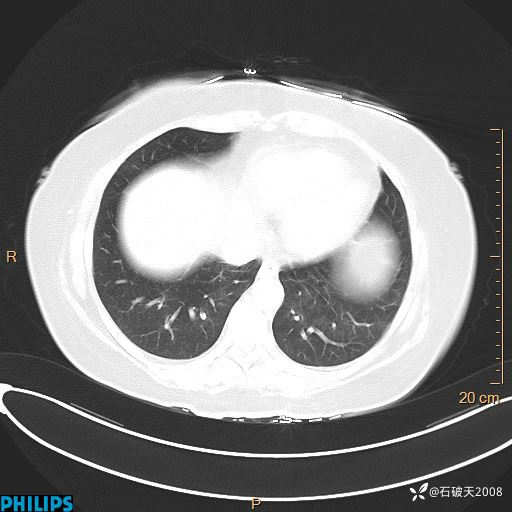

肺结节病?纵膈型肺癌?淋巴瘤?有点意思,欢迎围观

女 52岁 主 诉:咳嗽10余天,咳痰2天。

现病史:10余天前无明显诱因出现咳嗽,呈阵发性干咳,伴咽喉部发痒,无咽痛,无咳痰,无鼻塞、流涕、打喷嚏,无发热、畏寒、寒颤,无头痛、头晕,无胸闷、胸痛,无反酸、烧心,无腹痛、腹泻,无尿频、尿急,无皮疹等,在当地诊所求治,给予口服药物治疗(具体不详),病情无好转。遂在当地社区卫生服务中心开具口服药物治疗(具体不详),疗效欠佳。2天前出现咳痰,在我院门诊求治,行胸部CT提示肺部感染,建议住院,患者要求口服药物治疗,目前仍咳嗽、咳白色粘痰,白天量多,夜间自觉喉部喘鸣音,遂再次来院就诊,以“肺部感染”为诊断收入院。发病以来,神志清,精神可,饮食可,夜间睡眠差,大小便正常,近期体重无明显变化。

静脉期